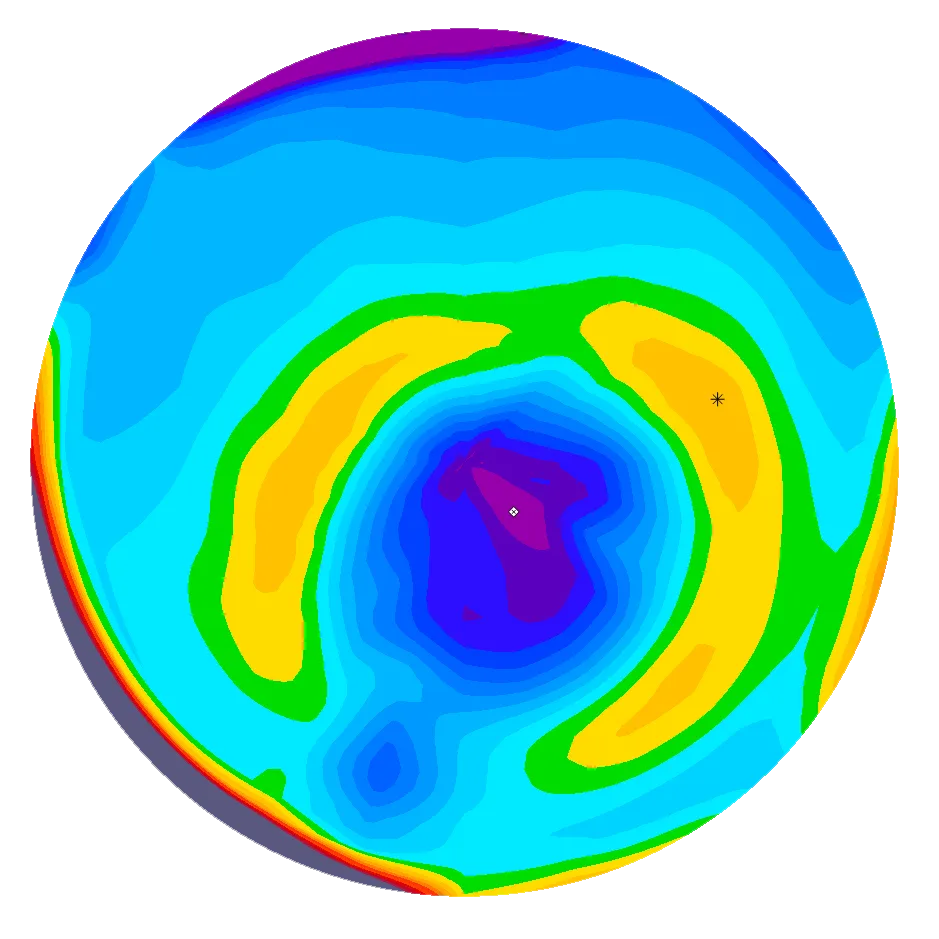

Diese Hornhaut ist erkrankt und benötigt weitere Untersuchungen/Behandlungen. Man erkennt, dass die Hornhaut im oberen Anteil flach ist und im unteren Anteil sehr stark vorgewölbt. Die Sehkraft ist verzerrt, es bestehen Doppel- oder sogar Dreifach- und Vierfach-Bilder und in vielen Fällen kann auch eine Brille die Sehschärfe nicht mehr wiederherstellen. Zudem ist die Krankheit fortschreitend und kann vor allem bei Kindern und Jugendlichen bis zu schwersten Sehbehinderungen führen.

Dank neuester Technologien sind wir heute in der Lage, sowohl die vordere als auch die hintere Oberfläche der Hornhaut mit extrem hoher Präzision zu messen. Dank dieser verbesserten Genauigkeit können Anomalien bereits in sehr frühen Stadien erkannt werden, was zu schnelleren und zuverlässigeren Diagnosen führt. Erkrankungen wie Keratokonus oder Pellucid Marginal Degeneration (PMD) lassen sich nun deutlich früher als bisher diagnostizieren, was die Patientenergebnisse verbessert und eine rechtzeitige Behandlung ermöglicht.

Das MS-39 kombiniert Hornhauttopographie mit hochauflösender OCT (optische Kohärenztomographie). Es liefert uns ein extrem detailliertes Bild der Hornhautschichten, mit dem wir subtile strukturelle Veränderungen erkennen und ein Fortschreiten im Laufe der Zeit überwachen können.

Die moderne OCT-Technologie für den vorderen Augenabschnitt bietet eine ultrahochauflösende Darstellung des Hornhautgewebes und ermöglicht eine unglaublich detaillierte Visualisierung seiner Struktur. Dieses Mass an Präzision ist ein grosser Vorteil bei der Nachsorge von Hornhauterkrankungen und der postoperativen Überwachung. Sie ermöglicht es den Ärzten, subtile Veränderungen der Hornhaut im Laufe der Zeit mit grosser Genauigkeit zu verfolgen.

Einer der wichtigsten Vorteile dieser Bildgebung ist die Möglichkeit, Hornhautnarben nicht nur hinsichtlich ihres Vorhandenseins, sondern auch ihrer Tiefe und Ausdehnung innerhalb der Hornhautschichten zu beurteilen. Solche detaillierten Informationen sind entscheidend für die Bewertung der Auswirkungen auf die Sehqualität und für die Planung künftiger Behandlungsstrategien, falls erforderlich.